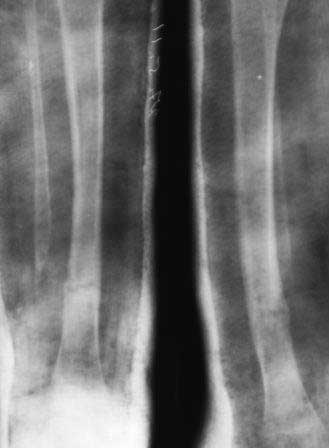

Девочка 2005г.р. В середине 2008 г падает с велосипеда с дедом, возможно был перелом н/з костей левой голени, лечение у знахаря-табиба, но ребенок не смог бегать, часто падал, начал хромать. Май 2009г. обратились к нам, установлен д-з « вялоконсолидирующаяся перелом н/з б/берцовой кости, несросшийся перелом м/берцовой кости со смещением по ширине». Мы решили гипсовая повязка и ходьба с нагрузкой, но по категорическому требованию родителей исправить деформацию м/берцовой кости, произвели операцию ( на свою голову )»о/ репозиция и и/м фиксация спицами м/берцовой кости». Теперь началась самая интересная история! Ч-з недели две в обл. п/о раны м/берцовой открылась свищ с кровянистым выделением, гноя не было, на р-грамме лизис концов отломков м/берцовой кости, к-рый начал прогрессировать, консультирована онкологами, цитология, с подозрением направлена в центральные институты, сделана КТ, онкологическое исключили, в августе попали в остеомиелитический центр, где произведена резекция м/б на протяжение 6-7см, все зажило и выписали (снимок-1). 2010г в мае повторно получила травму, наложена гипсовая повязка (снимок-2) и через 1-2 месяца в одном из центральном институте произведена КДО аппаратом Илизарова , который снят ч-з три месяца (снимок-3) и долго ходила на костылях-мать заставила, как начала наступать, появилась деформация, заказали ортез и так ходила, но деформация прогрессировала, Обратилась к нам в апреле 2012г,(снимок-4) произведена постепенная коррекция на аппарате, и замена на БИОС 01.03.12г плечевым гвоздем, ЭОП нет, поэтому осталась несколько антекурвация (снимок-5), ребенок ч-з неделю начала ходить.Повторный осмотр 22.06.12г- деформация усиливается, за три месяца сращение очень слабое.(снимок-6). (Жаль что многие р-снимки не сохранились, мать обещала хотя бы часть найти)!